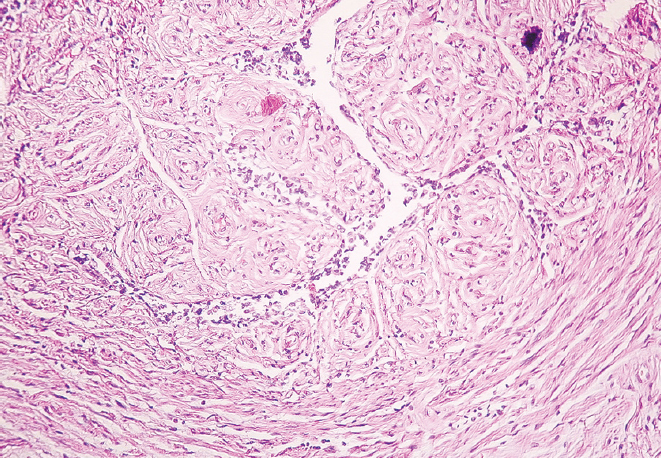

Перешеек и воронка маточных труб женщин старческого возраста характеризуются наличием утолщенных складок слизистой оболочки и уплощенным эпителием. Наблюдается неравномерное сужение просвета как в перешейке, так и в воронке, обусловленное близким друг к другу расположением складок слизистой оболочки, частично объединенных между собой. В старческом возрасте циркулярный и продольный слои мышечной оболочки выглядят истонченными в сравнении с образцами, взятыми для исследования у женщин молодого возраста. Наряду с этим у женщин старческого возраста выявлено разрастание соединительной ткани в стенке маточной трубы как в области воронки, так и в области перешейка. Видны скопления адипоцитов, локализующихся в подсерозной основе, где сосуды в утолщенной стенке располагаются группами (рис. 3, 4).

Рис. 3. Фрагмент перешейка маточной трубы женщины в возрасте 86 лет. Окраска гематоксилином и эозином, увел. ×10